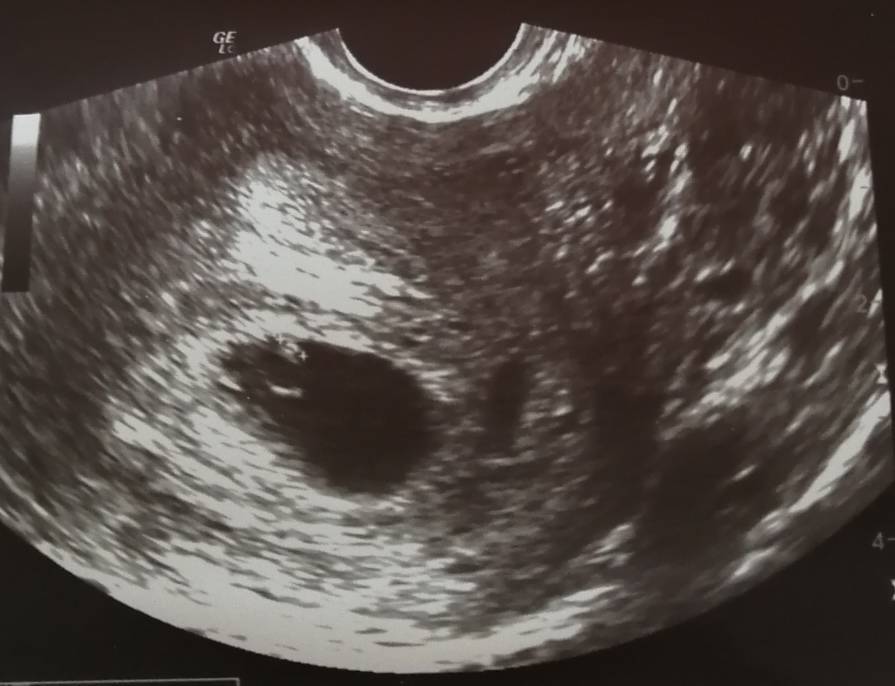

Dobra wiadomość: Zarodek jest prawidłowo zagnieżdżony i ma 2,5 mm [emoji3059] kamień z serca, jak tylko zobaczyłam mojego kropka zakochałam się na maxa [emoji3590]

Zła wiadomość: mam torbiel na prawym jajniku 3,8 mm [emoji26]

No i jeszcze zdjęcie, mam nadzieję, że się dopatrzycie tego mojego malutkiego kropka [emoji3059]

No i jeszcze zdjęcie, mam nadzieję, że się dopatrzycie tego mojego malutkiego kropka [emoji3059]Zobacz załącznik 1013467